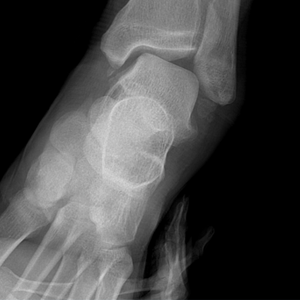

만성 인대 불안정성

다리 삐끗하는 게 일상이라면 '만성 발목 불안정성'을 의심해 봐야 한다.

만성 인대 불안정성  이미지